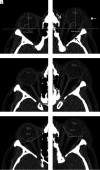

FIG 2.

Representative case with traumatic left-sided OCS due to intraorbital hematoma in the extraconal space (white arrow) and in the subperiosteal space (black arrow). Imaging is helpful to differentiate intraorbital hematoma from periorbital hematoma (dashed white arrow), which is anterior to the orbital septum and therefore does not lead to compartment syndrome. Intraorbital hematoma in this case results in increased proptosis (A and B), optic nerve stretching (C and D), and a decreased posterior globe angle (E and F). Besides stretching of the optic nerve, subtle thinning of the nerve and loss of normal undulation can be observed. Note that the angulation is slightly different for each side because the planes of measurement were reconstructed separately relative to the respective anatomic landmarks.